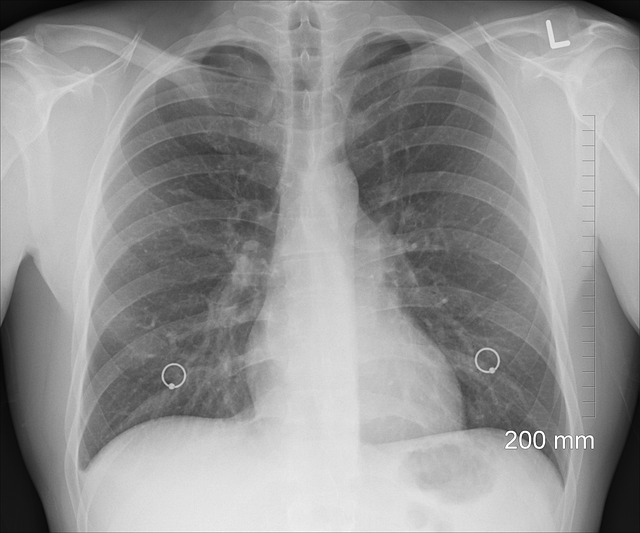

Osłuchiwanie płuc to metoda diagnostyczna polegająca na słuchaniu dźwięków wydawanych przez płuca i oskrzela za pomocą stetoskopu. Lekarz może ocenić, czy dźwięki są prawidłowe, czy występują jakieś nieprawidłowości, takie jak trzeszczenia, świsty czy szmery oddechowe. To pozwala na wczesne wykrycie różnych chorób płucnych, takich jak astma, zapalenie płuc czy obturacyjna choroba płuc.

Po umieszczeniu stetoskopu na klatce piersiowej, zacznij słuchać dźwięków płuc. Skup się na regularnym oddechu pacjenta i zwracaj uwagę na wszelkie nieprawidłowości, takie jak trzeszczenia, świsty czy szmery oddechowe. Możesz porównać dźwięki z obu stron klatki piersiowej, aby sprawdzić, czy są symetryczne.